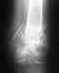

Здравствуйте.Не могли бы Вы мне помочь и ответить на мои вопросы?Мне 26 лет. 178см. 74кг. До определённого момента каких-либо проблес со здоровьем никогда не было. 26 декабря 2006 года я попал в аварию: ЗЧМТ, СГМ, повреждение Монтеджи (справа), закрытый оскольчатый перелом в\3голени. 1-н месяц с переломом ноги лежал на вытяжении - не помогло. 14.02.2007 года в травмотологии поставили аппарат Илизарова. На руку наложили пластину. До настоящего времени ношу аппарат. При ходьбе пользуюсь костылями. Полную нагрузку на поломанную ногу не даю. Каких-то особых болей нет. Воспалений, отёчности, покраснений и т.п. тоже нет. Пальцы двигаются. Всё где надо сгибается. По внешнему виду обычная, здоровая нога. Волнует то, что какого-либо срастания нет. Снимки делаю раз в месяц. Костной мозоли нет, то есть не видно её! Полную нагрузку на ногу не даю потому, что несколько раз консультировался с врачами и те высказывали совершенно разные мнения о ней, о нагрузке, да и вообще о сроках выздоровления, последствиях травмы. Ещё, и я сам очень боюсь полностью наступить на ногу. Какого-то доверия к устойчивости осколков у меня нет. Боюсь только нагрузкой всё усугубить. Ещё одна проблема в том, что в силу некоторых причин я не могу регулярно посещать своего лечащего врача-травматолога. Да ещё - я пью всевозможные комплексные витамины, кальций, мумиё, БАДЫ. Эффекта пока не вижу. Последний снимок голени прилагаю. Касательно перелома руки. Сращивание костей в порядке. Единственное, что беспокоит, это то, что после снятия гипса угол разгибания сустава составлял примерно 95%, За всё время я смог разработать до 140%.Если Вас не затруднит, то ответьте, пожалуйста: 1. Необходима ли полная нагрузка на поломанную ногу, т.е. ходьба без костылей? 2. Есть ли какие-либо причины того, что за 5-ть месяцев не образовалась костная мозоль? 3. Существуют ли какие-либо сроки сращивания переломов голени такого рода. 4. Может быть, стоит уже к этому времени паниковать и не сидеть дома, а искать самую дорогую клинику? Заранее спасибо всем тем, кто со вниманием отнесётся к моей проблеме. Буду рад получить от Вас любые полезные для меня рекомендации. Всего доброго. E-mail: vitebsk.hdv@mail.ru http://rb.foto.radikal.ru/0707/31/9117ba0393f6.jpg

Многооскольчатый перелом голени со смещением. Как мне ускорить процесс заживления? Какие принимать препараты ?Сколько ходить в Илизарове? С момента перелома 2 месяца. Снимок сделан после компрессии. Даю нагрузку 22кг.

По этому снимку не очень хорошо видно, похоже, вовлечена суставная поверхность. Надо делать КТ. Возможно, что-то надо будет еще сделать, если форма суставной поверхности не восстановлена. А есть снимок до наложения аппарата?